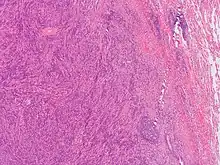

Since plasma cell granulomas have the ability to occur at any site, even though they are uncommon, it should be included in differential diagnostics in regard to plasma cell neoplasms.[3] With granulomas that arise in the mouth, PCGs are commonly misclassified considering the malignancy of the disease due to its aggressive behavior and clinical presentation.[4] Plasma cell granulomas located in the oral cavity have been identified with disruption and damage of surrounding tissues.[4] In comparison, PCGs manifesting in other internal organs are usually secondary findings on radiographic images.[4] Occasionally, plasma cell granulomas are misdiagnosed as malignant lymphoma or malignant plasmacytoma during initial examination due to radiological evidence of its ability to erode and infiltrate bone.[4] Typically, under microscopic analysis, a plasma cell granuloma will display a dense population of morphologically similar plasma cells sporadically mixed together with other inflammatory lymphocytes seen in a storiform orientation of fibrotic connective tissue.[3][4] To avoid the misdiagnosis of a PCG as a plasmacytoma, it should be noted PCGs are formed from typical plasma cells while plasmacytomas consist of both atypical and typical plasma cells.[4] It is imperative that such differentiation between plasma cell granuloma and plasmacytomas are completed prior to informing the patient undergoing clinical examination.[4] The importance of an accurate diagnosis between the two is due to the different prognosis and progression of the mass-forming lesions.[4] While plasma cell granulomas are often found to be benign, plasmacytomas have been associated with a more aggressive and invasive behavior in which they have the ability to transform or evolve into multiple myeloma.[4] One of the most reliable distinguishing factors from plasmacytomas and plasma cell granulomas, is the polyclonality of the plasma cells involved with plasma cell granulomas.[3] PCGs that manifest in the mouth, specifically the gingiva, have been seen to exhibit similar physical characteristics of other conditions such as epulis, fibroma, pyogenic granuloma, and peripheral giant cell granuloma.[4] Histopathological analysis of plasma cell granulomas have been found to be the most precise confirmative diagnosis to distinguish PCGs from other lesional tumors of plasma cell origins.[4]

Analyzing the changes that arise in the tissue associated with the mass-forming lesion has been found to be the most accurate and precise method for confirming the diagnosis of plasma cell granulomas. This can be achieved by taking excision biopsies of the unknown mass for examination.[4] Typically, plasma cell granulomas appear microscopically as a lesional mass consisting of an abundance of plasma cells intermingled among different inflammatory cells set in fibrous connective tissue displayed in a spiral appearance.[3][4] Depending on the location of the plasma cell granuloma, vasculitis can be present but is not considered a confirmatory factor for diagnosis.[3] Kappa/lambda in-situ hybridization is another diagnostic test that needs to be done when trying to characterize the lesion for further confirmation.[3] Common results associated with kappa/lambda in-situ hybridization studies of PCGs are an abundant population of CD138 positive polyclonal plasma cells.[3] If instead, results show monoclonality of plasma cells it is indicative of plasmacytoma.[3]